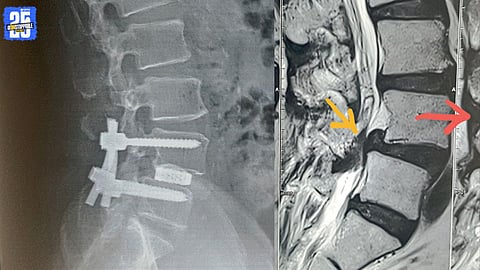

मागच्या आठवड्यात लिहिलेल्या लेखामधल्या लक्षणाप्रमाणे दिसणारी लक्षणं असणारा मणक्याचा आणखी एक आजार म्हणजे स्पाँडिलोलिस्थेसिस. ‘‘डॉक्टर, गेले काही महिने माझी कंबर विलक्षण दुखते आहे... खरंतर याची सुरुवात दीड वर्षापूर्वी झाली. मी भाजी आणायला म्हणून बाहेर पडले आणि नेहमीचा भाजीवाला नव्हता म्हणून दीड किलोमीटर चालत पुढे गेले. घरी परत येताना कमरेचा खालचा भाग दुखायला लागला आणि मांड्या व पोटऱ्या यात जडपणा जाणवायला लागला.